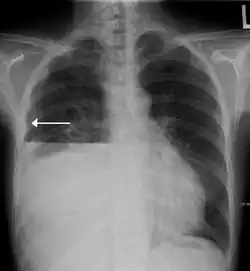

A hydropneumothorax with a white arrow pointing to the lung's pleura | |

Hydropneumothorax is defined as the presence of both air and fluid within the pleural space.[1] An upright chest x-ray will show air fluid levels. The horizontal fluid level is usually well defined and extends across the whole length of one of the hemithorax.